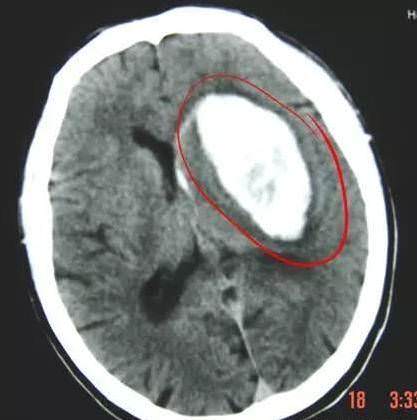

腦出血,是中風的另一種,稱為出血性腦卒中,簡單說,就是腦子裡的血管破裂出血了。

60歲的王大爺在家裡和兒子爭吵後,突然暈倒,送往醫院後是腦出血。

腦出血的症狀較重,且 預後相對不佳,一般常見有頭痛、頭暈、嘔吐等症狀,血壓明顯升高,嗜睡、昏迷甚至出現癲癇,其 身亡率相對較高, 復發率相對較低。